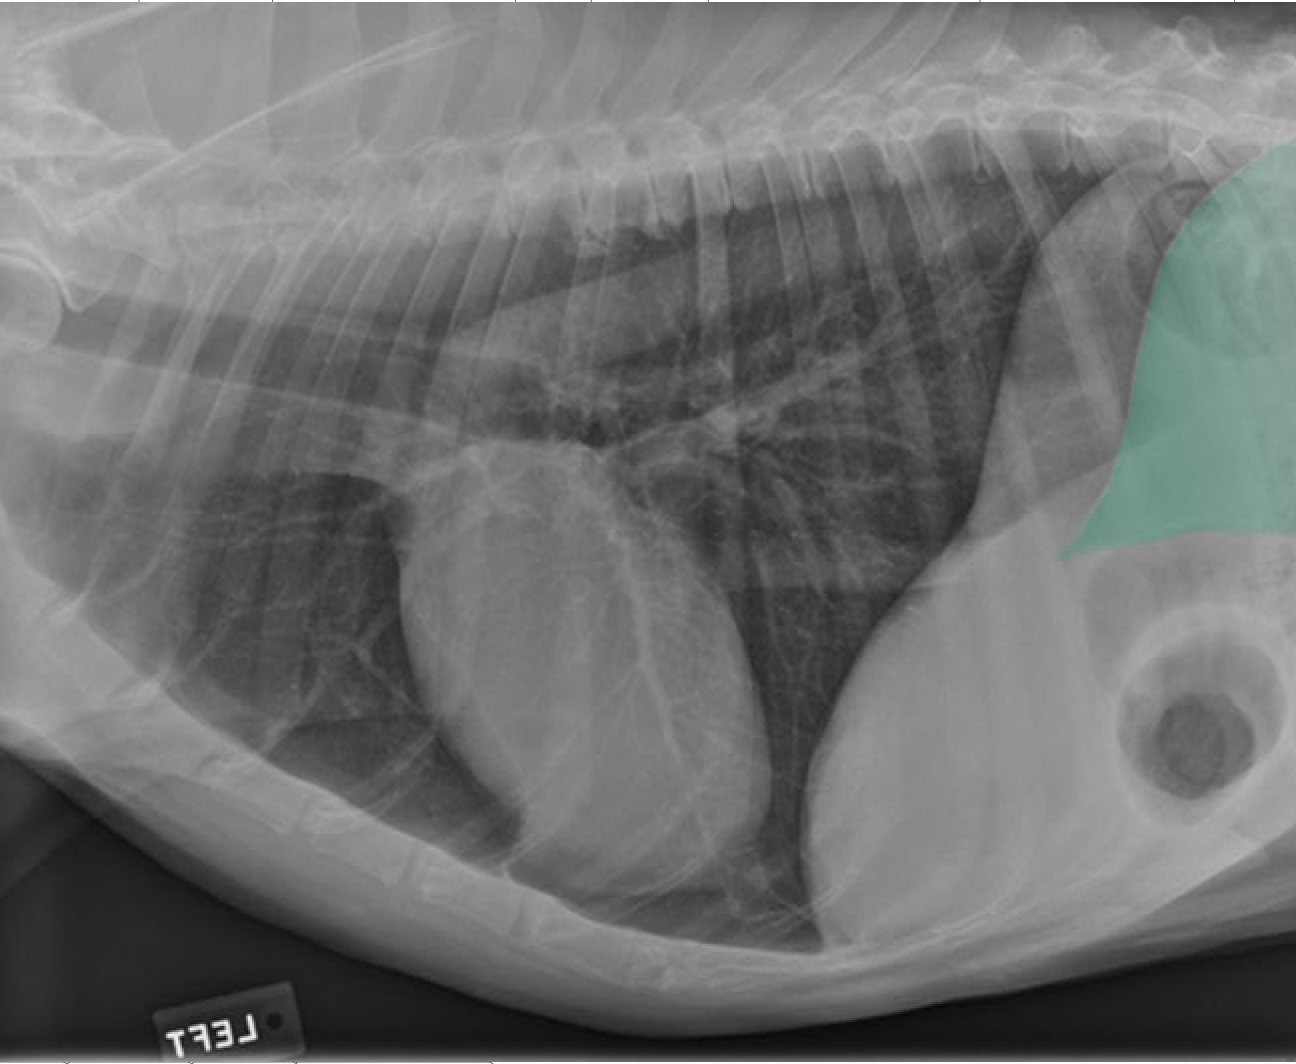

identity the structures on the thorax radiograph left lateral view

heart

identify the right cranial pulmonary vein

identify the pulmonary arteries

identify the right cranial lung lobe

identify the right cranial bronchus

identify the right accessory lobe of the lung

identify the right crus of the diaphragm

identify the left crus of the diaphragm

identify the dome of the diaphgram

identify the left cranial lung lobe